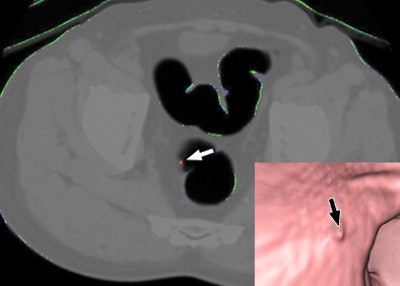

| Examples of false-negative lesions by computer-aided detection (CAD). A 10-mm flat adenomatous polyp in sigmoid colon was missed by CAD. Axial 3D endoluminal (right lower corner). Supine CT colonography images show polyp (arrow) that is not tagged with red. Republished with permission of the © American Roentgen Ray Society, by Se Hyung Kim, Jeong Min Lee, Joon-Goo Lee, Jong Hyo Kim, Philippe A. Lefere, Joon Koo Han, and Byung Ihn Choi, from AJR 2007; 189:41-51). |